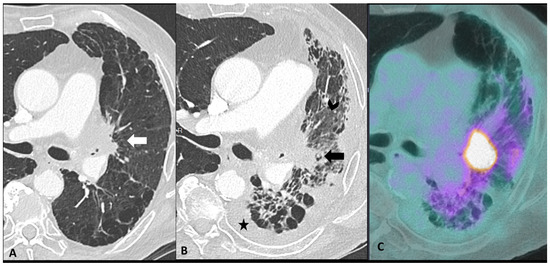

2.2.1. Ir-Pneumonitis

| Radiological Pattern | Main Radiological Findings | Main Radiological Clues and Tips | Main Differential Diagnosis | |

|---|---|---|---|---|

| Pneumonitis | OP | Multifocal, patchy, consolidations or GGOs with peribronchovascular and/or subpleural distribution | Migratory on a subsequent scan | Radiation Pneumonitis Infectious pneumonia Tumor progression |

| SPE | Scattered nodules or GGOs | Migratory and transient | Infectious Pneumonia | |

| Solitary Nodule | Nodule(s) | Mild metabolic activity at 18F-FDG PET/CT | Lung cancer Metastasis Infectious pneumonia including septic emboli | |